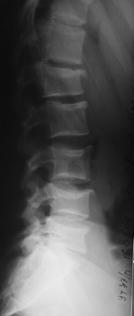

При переломах двух и более смежных позвонков устанавливали более протяженную фиксацию с опорой на интактные тела позвонков относительно травмированных. При многоуровневых повреждениях (травма двух и более позвонков, находящихся друг от друга на расстоянии минимум двух позвоночно-двигательных сегментов), использовали раздельную фиксацию каждой зоны, сохраняя подвижный сегмент между ними (рис. 11, 12).

Рис. 11. Рентгенограммы пациента С. 16 лет Взрывной перелом L1, L4, L5

А – до операции; Б – после транспедикулярной репозиции и фиксации Th12-L2, L3-S1 и заднего локального спондилодеза |